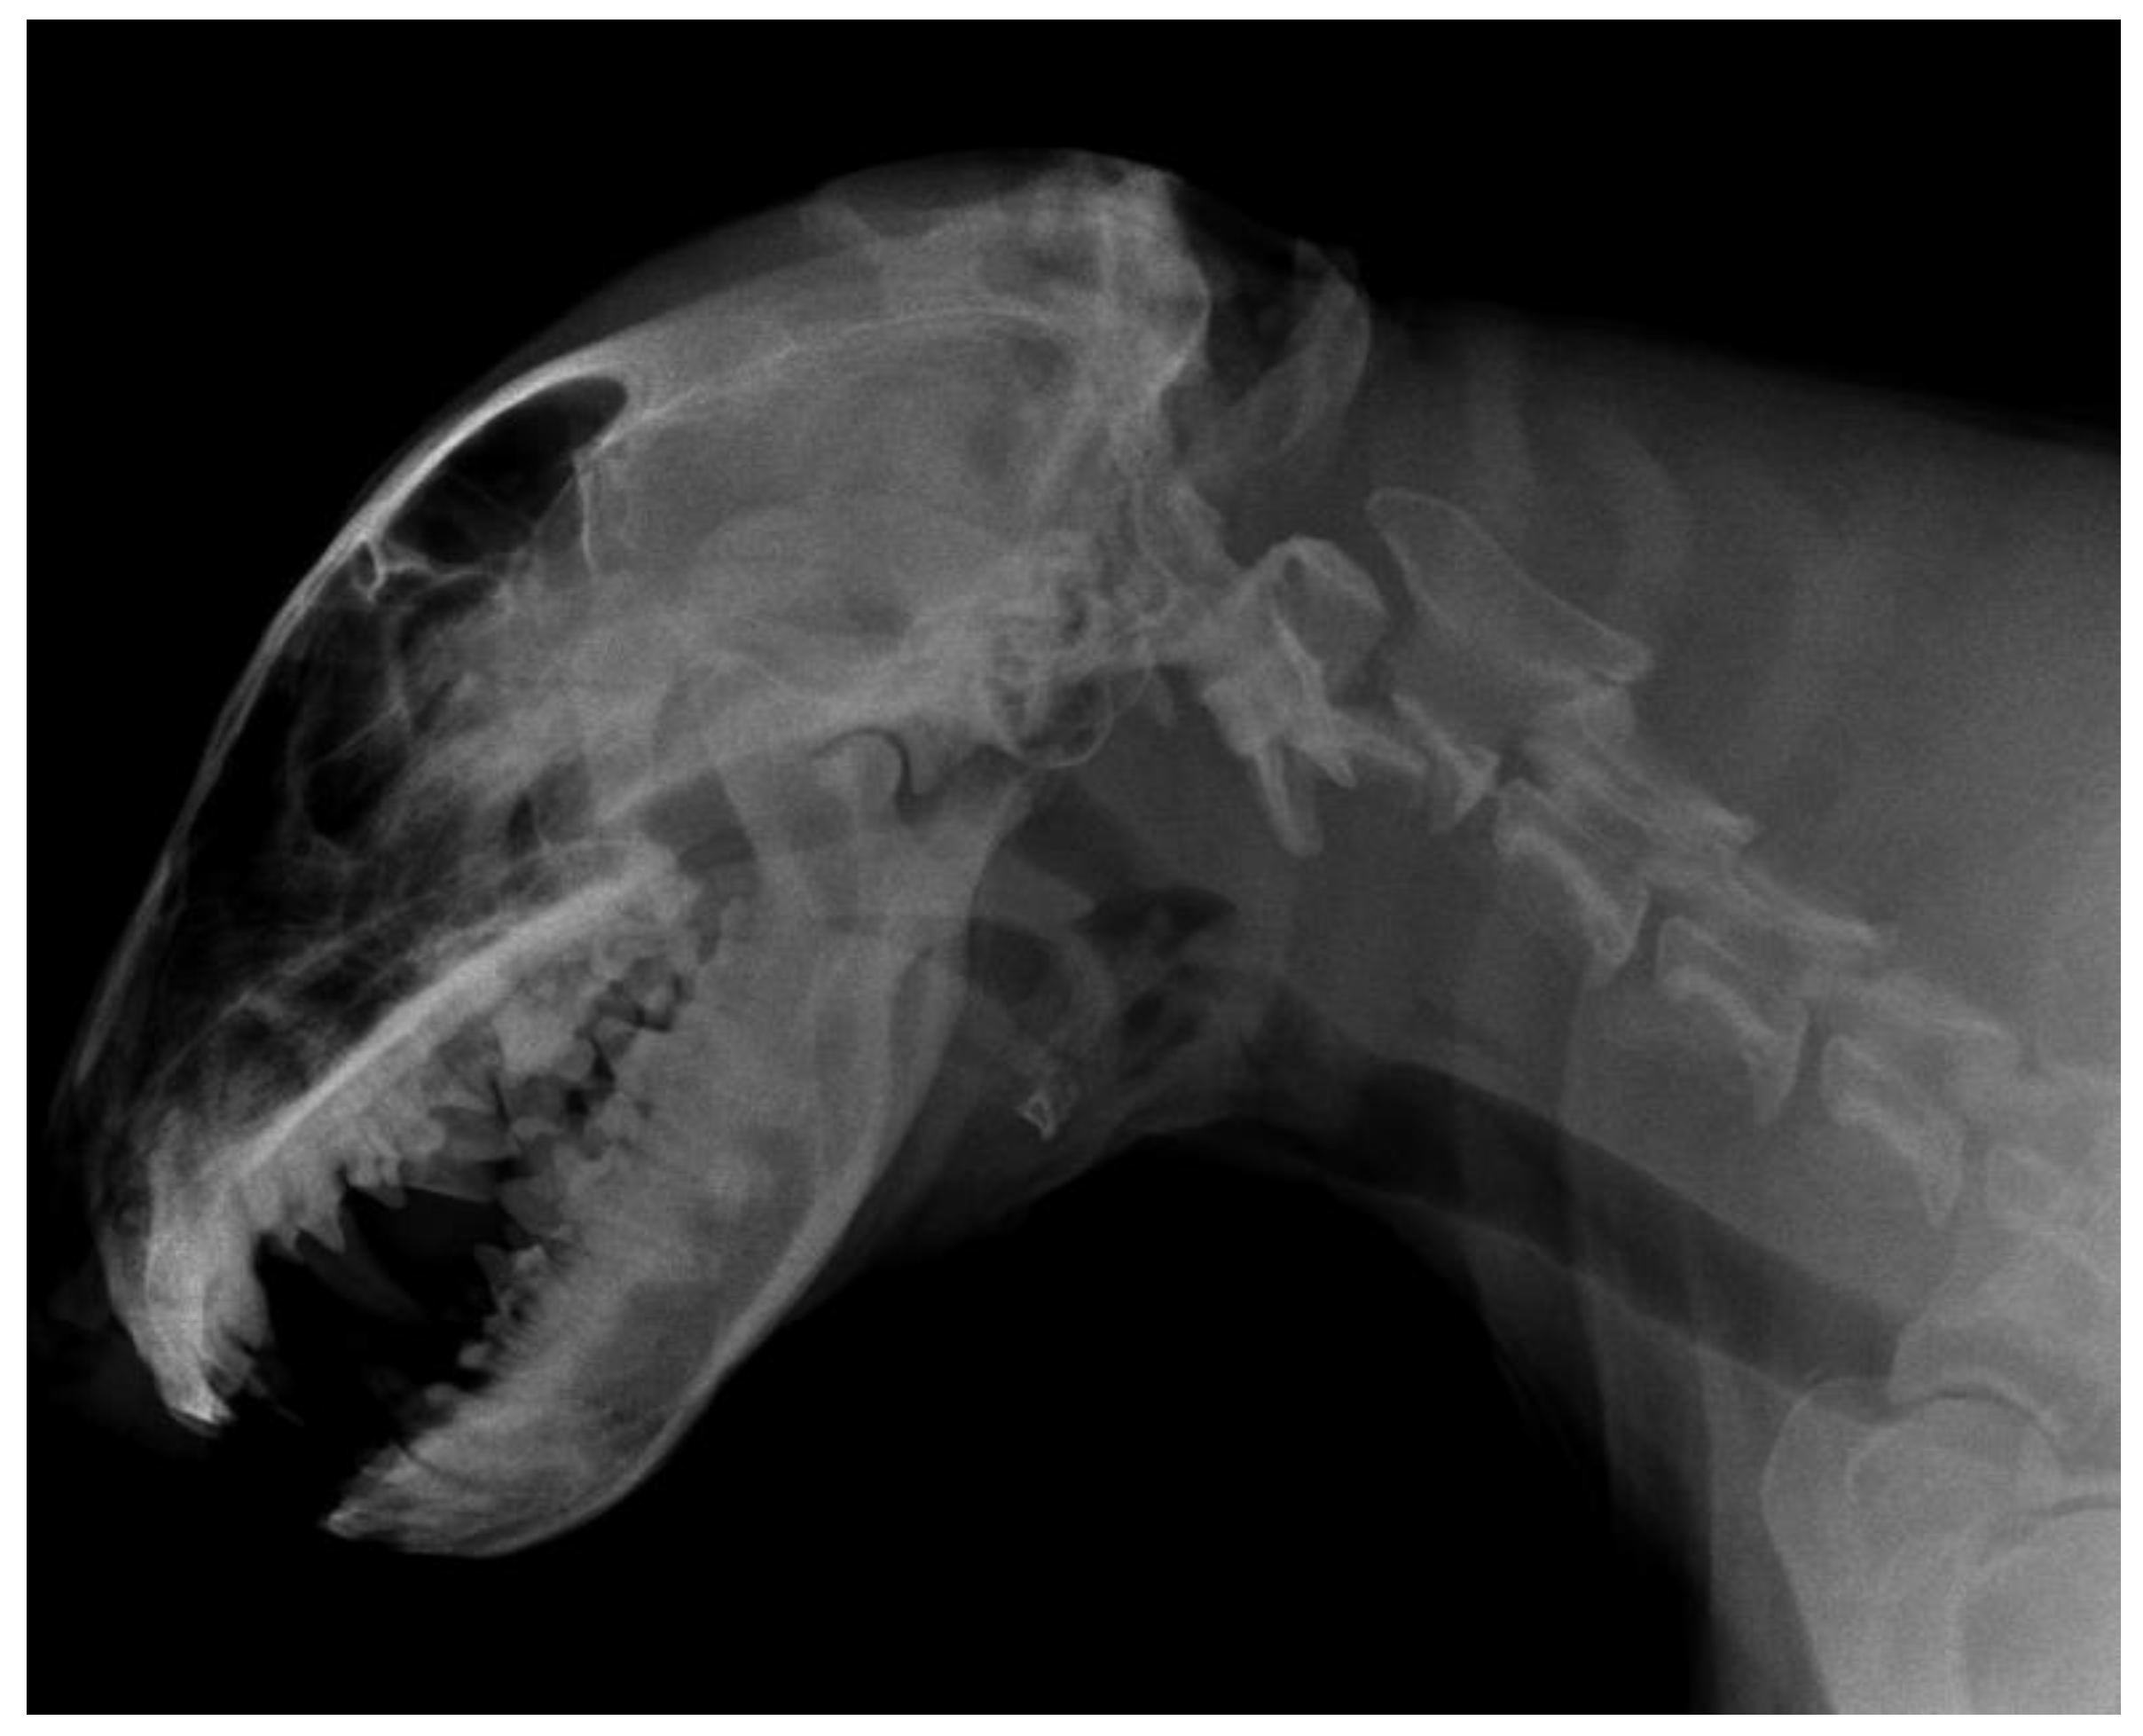

2.1. Imaging Protocols

3.2. Diagnostic Imaging